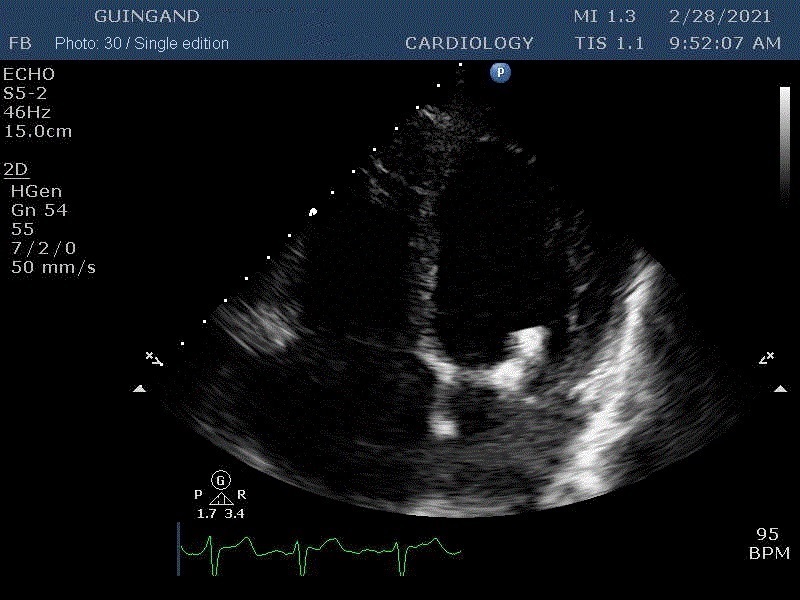

"Beats of my heart " NFT video

The very first heartbeat NFT to be sold in a marketplace The heart is the main vital organ of the human body. The expression “Put your heart into it” means to do something with sincere effort and passion. Guingand puts so much heart into everything he does — his life, his work, his relationships with others — that he has weakened his heart.

These are the first Cardiology NFTs for sale on a marketplace.

37 unique photos of the artist's most recent echocardiogram.

“Art is inside of us too.”